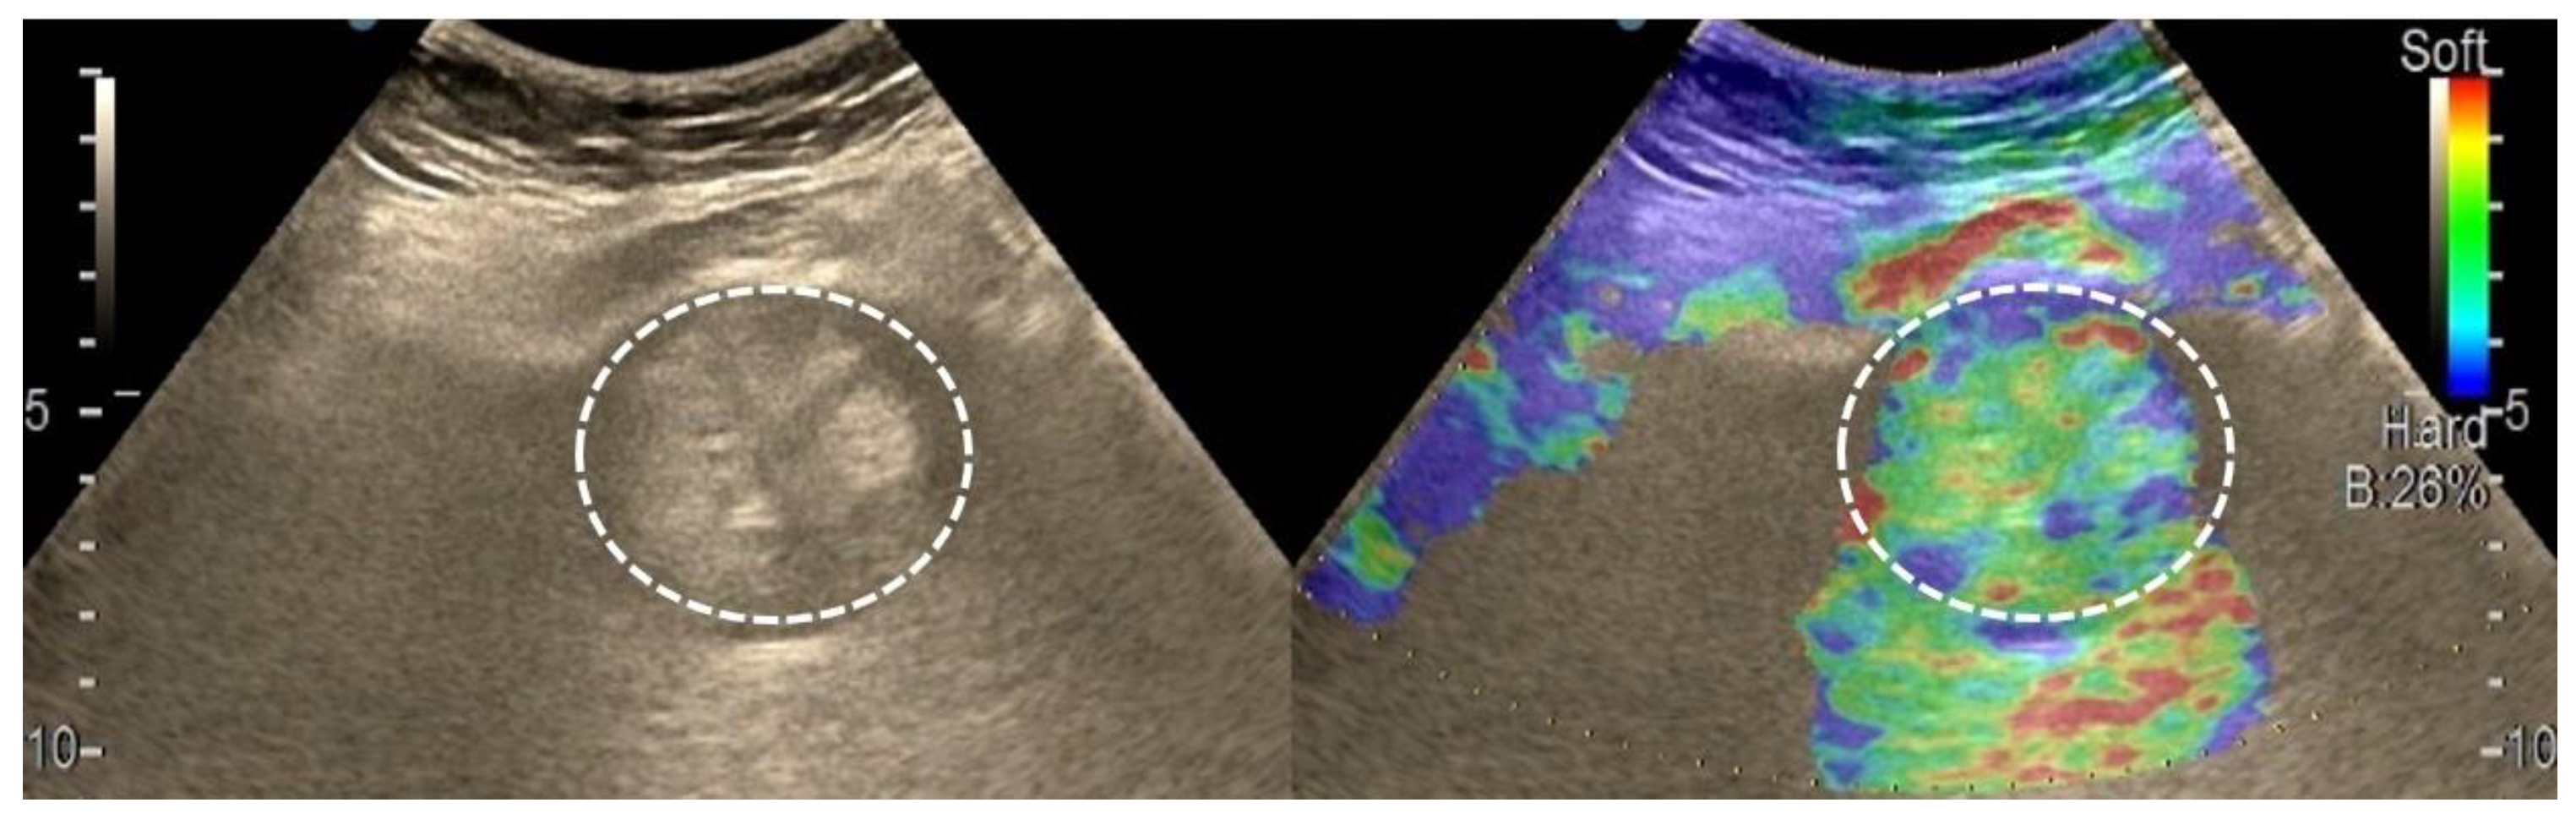

3.1. B-Mode Ultrasound

3.4. Real-Time Tissue Elastography